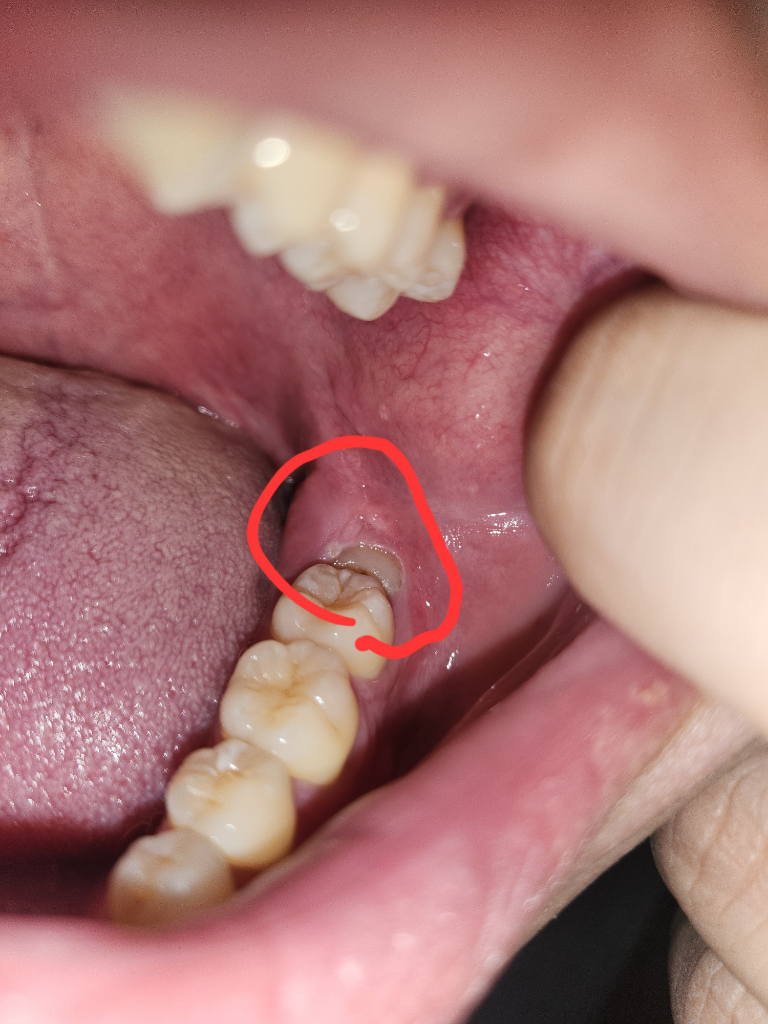

잇몸 혀 쪽에 구강암 일까요?

2일전에 양치질하다 혀 옆과 사랑니쪽이 아파서

봤더니 하얗게 뭐가 생겼어요

만지면 통증이 있습니다ㅜㅜ

구강암일까요??ㅠㅠ.